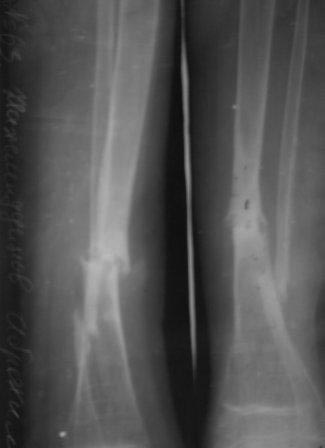

в районе лечили гипсом 6 месяцев, сращения нет, в обл.центре КДО аппаратом Илизарова - 3 месяца, после повторная деформация, в НИИТО КДО аппаратом Илизарова -7 месяцев, перелом якобы сросся, но после снятия аппарата через 2 недели после незначительной травмы повторный перелом. И родители начали лечиться у различных табибов и знахарей, мальчик не наступал, ходил с двумя костылями, одели различные ортезы и повязки, и нога сильно атрофировалась.(Мне кажется у ребенка был врожд. ложный сустав, латентная форма) , и в 2011 г, в октябре обратились к нам. , было произведена после рассверливания канала БИОС плечевым стержнем,но стержень пошел по мед.стенке дистального отломка поэтому остался некоторый вальгус(операция без ЭОП) ребенок через неделю начал самостоятельно ходить, клинически деформации нет, все обрадовались, выписали, повторно приехали только ч-з 1,5 года вот с такой деформацией, но ребенок ходит в школу, бегает, незначительно хромает, родители требуют исправить деформацию.

Пока в голове один план: удалить стержень, закрытая остеоклазия, аппарат Илизарова из двух колец постепенная коррекция деформации, рассверливание к/м канала, БИОС плечевым стержнем (чуть длиннее), дистально по латеральному кортексу с использованием поллерных винтов и спиц.